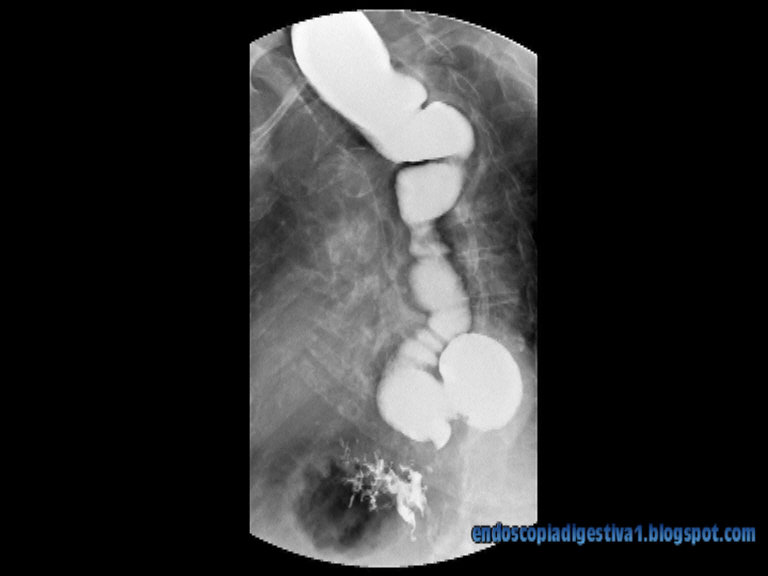

Paciente de 90 años de edad con antecedentes de HTA, DM tipo II, institucionalizada. En tratamiento con eprosartan, nifedipino, furosemida y esomeprazol. Desde hace años presenta disfagia lentamente progresiva a sólidos y líquidos que se ha acentuado en los últimos meses, donde se acompaña de pérdida de peso y episodios de broncoaspiración. Se realiza EGD donde se aprecia una importante diltación esofágica (megaesófago) con morfología sigmoidea e imagen distal en forma de «pico de loro» a nivel del cardias, donde además se aprecia por encima un gran divertículo epifrénico (probablemente por mecanismo de pulsión). Con el diagnóstico de achalasia evolucionada y con la intención de simplificar el las medidas diagnóstico-terapéuticas (dada la edad de la paciente), se decide realizar inyección de toxina botulínica (100 UI diluidas en 4 cc de SSF, con inyección profunda a nivel muscular en los 4 cuadrantes del cardias en alícuotas de 25 UI/inyección). El tratamiento se repite al mes con la misma pauta. La paciente evoluciona de forma favorable de la disfagia, consiguiendo una importante ganancia de peso a los 6 meses del tratamiento.